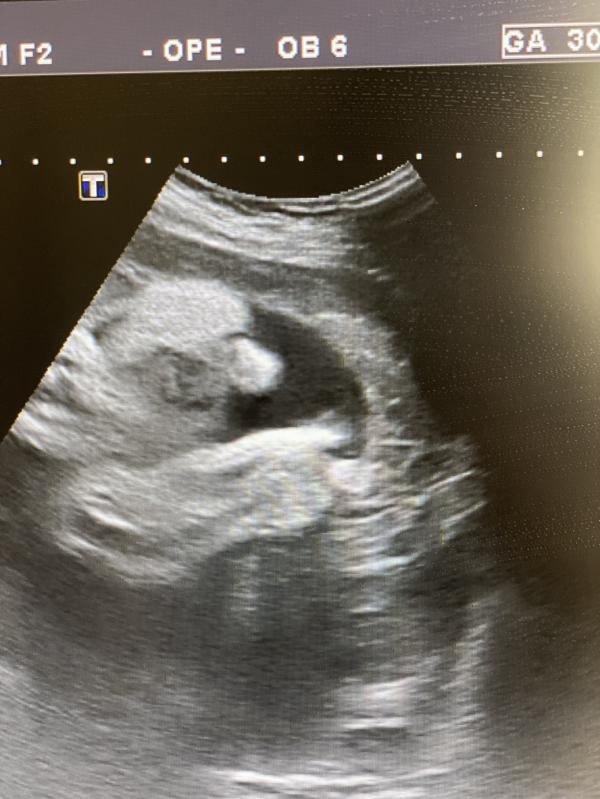

На узи узнала что 22 неделя беременности, девочки сказать что у меня был шок - не сказать ничего. У меня была истерика…

Я реально 22 недели абсолютно не чувствовала ничего. Живота не было.

В итоге скоро на свет появится Софи) ❤️

Сколько плод весит по узи? Если живота нет, плод отстаёт в развитии, так врачи говорят.